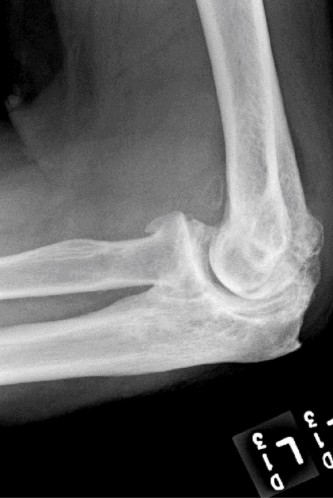

Clinical presentation typically involves progressive pain, stiffness, loss of motion (especially extension and flexion), mechanical symptoms like clicking or locking, and sometimes ulnar nerve irritation due to osteophyte encroachment. Diagnosis relies on a comprehensive history, physical examination, and radiographic evaluation demonstrating joint space narrowing, osteophytes, subchondral sclerosis, and possibly loose bodies.

- Standard Radiographs: AP, lateral, and oblique views are crucial for assessing joint space narrowing, osteophyte burden (anterior coronoid, posterior olecranon, radial head), subchondral sclerosis, and the presence of loose bodies. Weight-bearing views are not typically used for the elbow.

- Computed Tomography (CT) Scan: Highly valuable for complex OA, especially post-traumatic cases. Provides detailed information on bone morphology, the size and location of osteophytes, quantification of loose bodies, and assessment of bone stock for potential arthroplasty. 3D reconstructions are extremely helpful for visualizing complex deformities and planning osteophyte excision or implant placement.

| Radiographic Changes | Early OA: mild joint space narrowing, minimal osteophyte formation, no loose bodies. | Moderate to severe OA: significant joint space narrowing, large osteophytes (anterior/posterior), subchondral sclerosis, loose bodies, gross articular incongruity, subchondral cysts. |